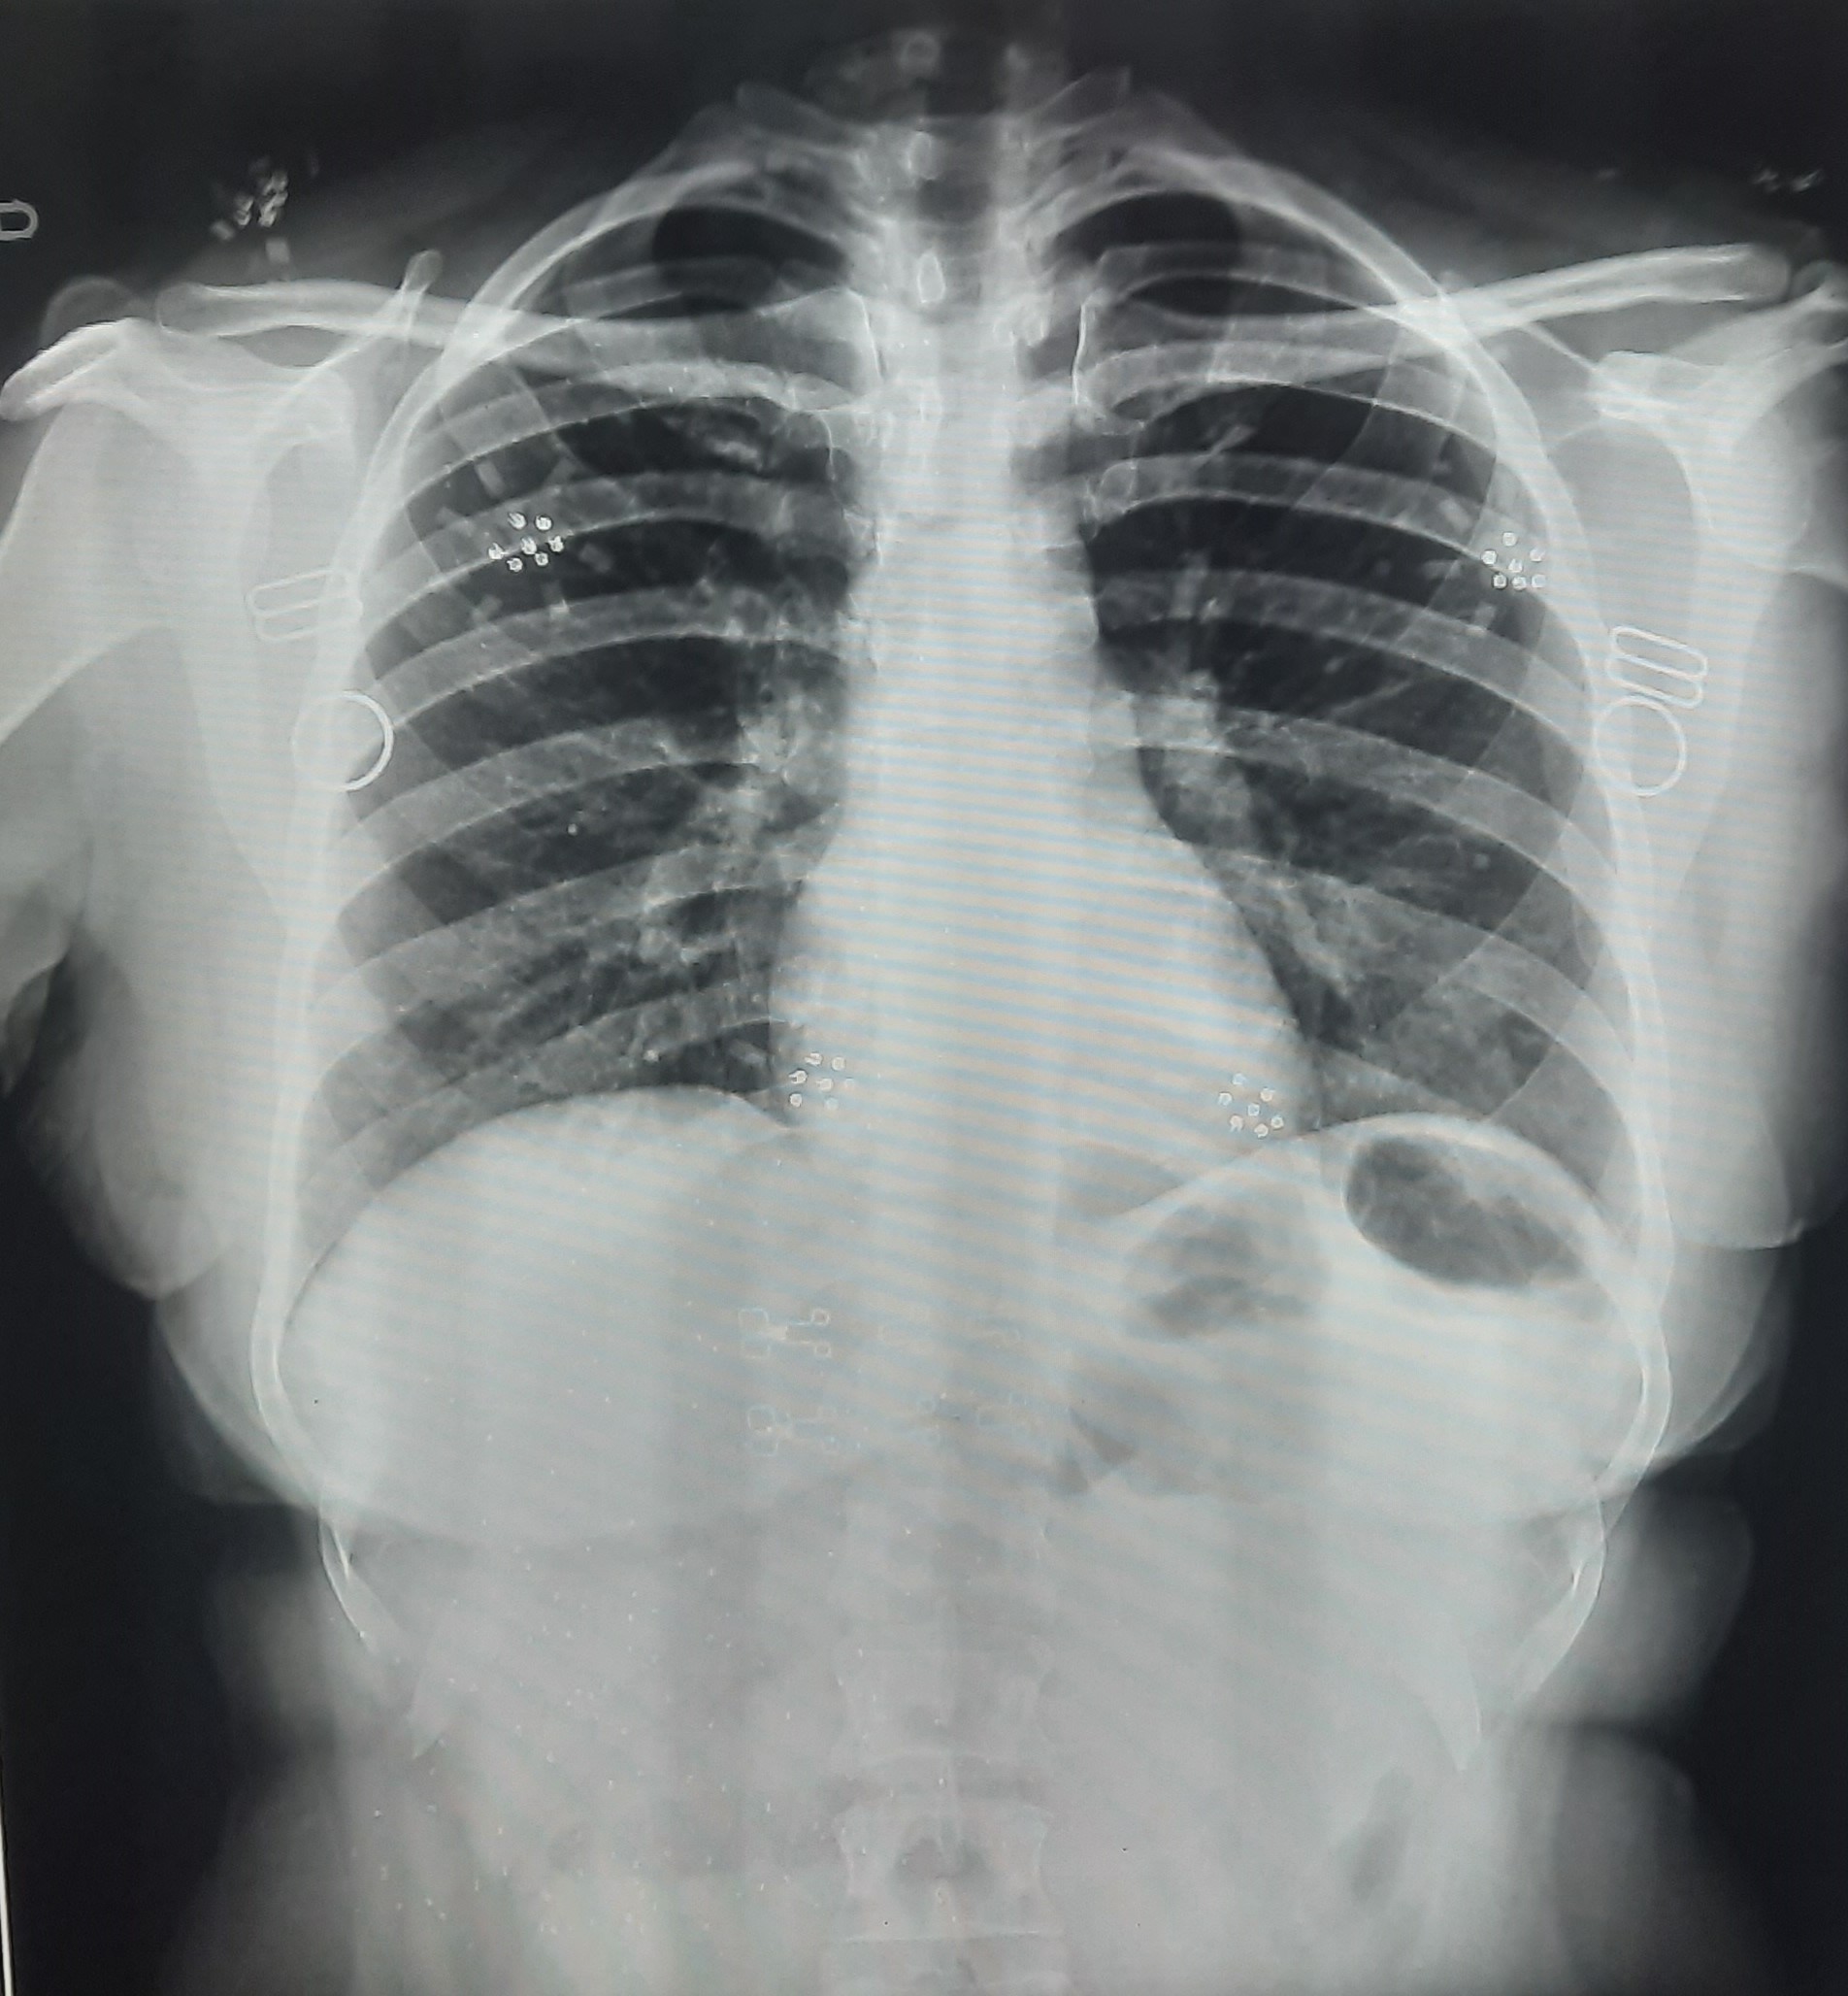

| 220 | IGGMC, Nagpur, Nagpur | P2 | 29-4252 | AMOL PAUNIKAR | Consent taken on Paper | 36 Yrs. |

Provisional Diag : BILATERAL INFILTRATION ? MILLIARY TB

Final Diag : MILLIARY TB |

TB Case (Confirmed) | MILLIARY TB | Abnormality visible on x-ray |

View |